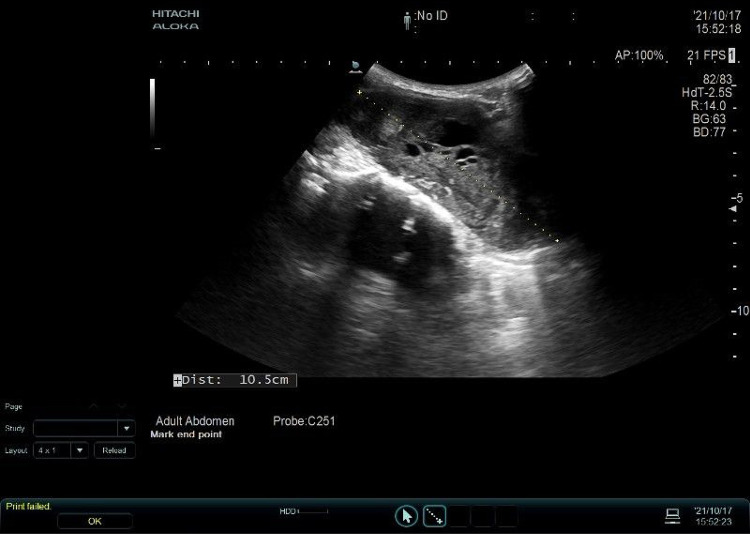

Case presentation: A 55-year-old female with no prior thyroid disease was diagnosed with advanced ATC after a routine check-up revealed a neck mass. She presented with a tumor compressing the trachea, recurrent laryngeal nerve, and carotid sinus, accompanied by Horner's syndrome. Fine-needle aspiration confirmed anaplastic sarcoma. After a multidisciplinary consultation, the patient was treated with anlotinib, tislelizumab, and albumin-bound paclitaxel, resulting in significant tumor shrinkage and symptomatic relief. However, due to financial constraints, treatment was discontinued. One month later, the tumor rapidly progressed, leading to tracheal compression and asphyxiation, causing her death.